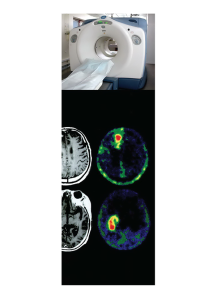

ในช่วงสองทศวรรษที่ผ่านมา มะเร็งเป็นสาเหตุการเสียชีวิตลำดับที่สามรองจากโรคหัวใจหลอดเลือดและอุบติเหตุ จำนวนผู้เสียชีวิตจากโรคมะเร็งแนวโน้มสูงขึ้นเรื่อย ๆ (1) จากข้อมูลของกระทรวงสาธารณสุขปี พ.ศ. 2548 โรคมะเร็งได้กลายเป็นสาเหตุการเสียชีวิตลำดับที่หนึ่งของประเทศ(2) สำหรับผู้ป่วยมะเร็งนอกเหนือจากการรักษาที่ได้มาตรฐานแล้วการวินิจฉัยโรคอย่างถูกต้องและแม่นยำสามารถนำไปสู่การรักษาที่เหมาะสม ทำให้ผู้ป่วยมีชีวิตที่ยืนยาวขึ้นหรือมีคุณภาพชีวิตที่ดีขึ้น ปัจจุบันมีการพัฒนาเครื่อง Positron Emission Tomography-Computed Tomography (PET-CT Scan) ซึ่งเป็นการถ่ายภาพทางด้านรังสีโดยใช้สารเภสัชรังสี ร่วมกับการถ่ายภาพเอ็กซเรย์คอมพิวเตอร์ (CI-Scan) ให้ภาพถ่ายที่แสดงโครงสร้างทางการภาพและการใช้พลังงานในระดับเซลล์ (cell metabolism) ที่ค่อนข้างชัดเจน ทำให้ PET-CT Scan สามารถหาเซลล์ที่ผิดปกติได้แม่นยำ (Accuracy) ด้วยความไว (Sensitivity) สูง ในปัจจุบันมีหลักฐานบ่งชี้ว่าเครื่อง PET-CT Scan มีประโยชน์สำหรับการวินิจฉัยและติดตามผู้ป่วยโรคมะเร็ง โรคสมอง โรคหัวใจและหลอดเลือด(3)